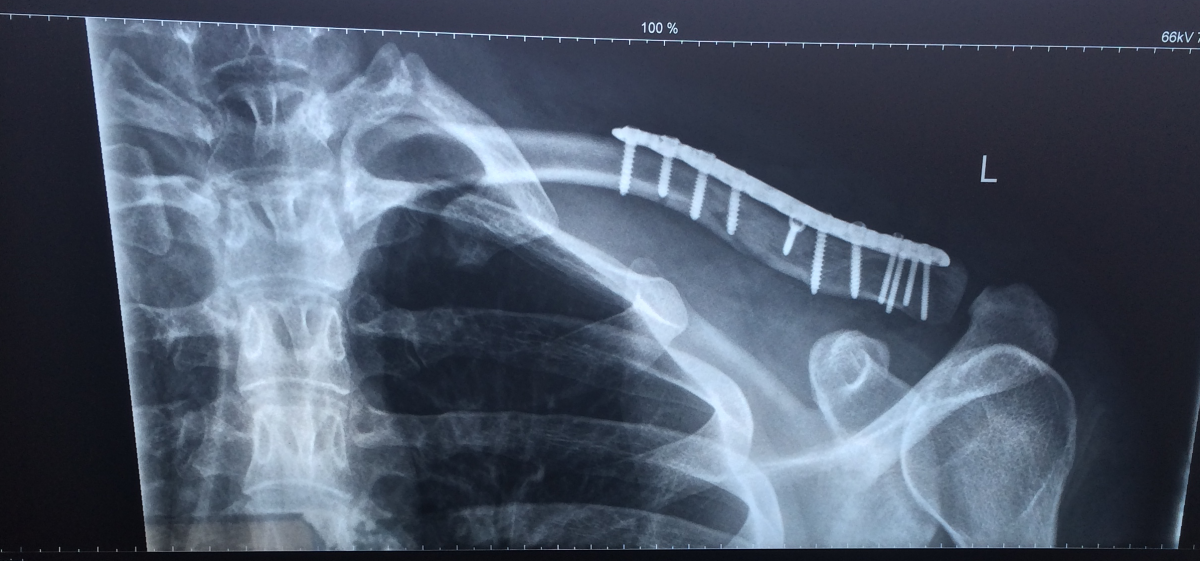

Ui, böse. Nene, nix getrümmert.Claviculafraktur /Trümmerbruch. Shit. Hatte ich auch mal - sah genauso aus. Bei mir wurde noch Knochen aus dem Hüftkamm eingesetzt!